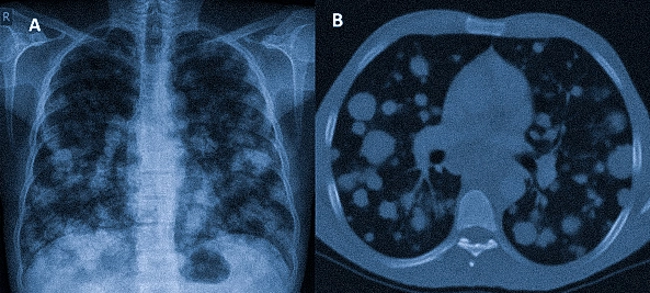

Если метастазами сильно поражены лёгкие или плевра, у пациента может возникнуть одышка, скопление жидкости вокруг легких (гидроторакс) кашель, ощущение нехватки воздуха.

на снимках: множественные метастазы в легких Если опухоль разрослась в кишечнике, возможна кишечная непроходимость, когда нарушается прохождение каловых масс по кишке, сильные боли в животе, интоксикация.